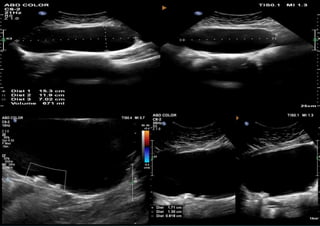

<10 cm

Serous cystadenoma

unilocular, regular walls, <10 cm